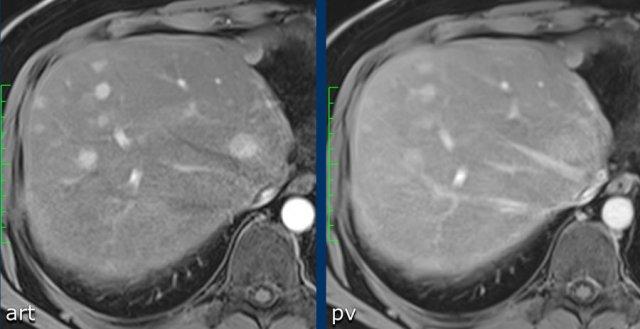

Hãy phân tích các hình ảnh MRI.

Đâu là các phát hiện chính và đâu là các phát hiện bổ sung?

Bạn sẽ cho điểm LI-RADS như thế nào?

Đặc điểm chính – làm cho đây là tổn thương LR-5:

- Tổn thương > 20mm

- APHE không dạng viền (non-rim APHE)

- Thải thuốc (washout)

Đặc điểm phụ trợ – sẽ được thảo luận sau:

- Hạn chế khuếch tán (mũi tên).

- Cấu trúc khảm (mosaic architecture) – thấy trên thì muộn.

Dưới đây là các phát hiện đã được điền vào bảng:

Đây là tổn thương LR-5.

Trong tổng số các tổn thương LR-5, 95% là HCC và 98% là ác tính.